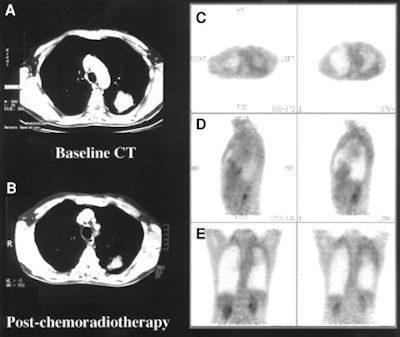

The Australian researchers presented a second study in the same issue, using similar methods to assess whether FDG-PET is useful and predictive of outcome in patients who have undergone potentially curative therapy (Journal of Nuclear Medicine, November 2001, Vol. 42:11; pp. 1605-1613).

In 63 NSCLC patients with suspected relapse more than six months following therapy (mean: 19 months), they compared restaging with conventional imaging and pathological results to those methods with the addition of PET imaging. The Cox proportional hazards regression model was used to evaluate the prognostic significance.

PET findings were positive in 41 of 42 patients with confirmed relapse, with sensitivity of 98%, specificity of 82%, and overall accuracy of 93%. Over 12 months, no disease was found in 14 of 15 patients with clinically suspected relapse but who received a negative PET scan, resulting in a negative predictive value of 93%.

PET results altered disease management significantly in 40 patients, including 6 who were changed from curative to palliative care after PET showed more extensive disease than had been shown on conventional evaluation. Moreover, 8 patients were spared active palliative therapy that was being considered until PET results showed no recurrence of disease.

The authors found that PET is superior to conventional staging alone in assessing disease status, stratifying prognosis, and selecting patients for treatment, and thus affects patient management significantly.

"Our study suggests that PET, in addition to accurately confirming or excluding disease relapse, more accurately assesses the distribution of disease than do conventional techniques," the authors wrote. "This accuracy is particularly important in patients for whom the PET result altered management."

PET should be performed on patients with suspected relapse following treatment, they concluded, particularly when active treatment is being considered.